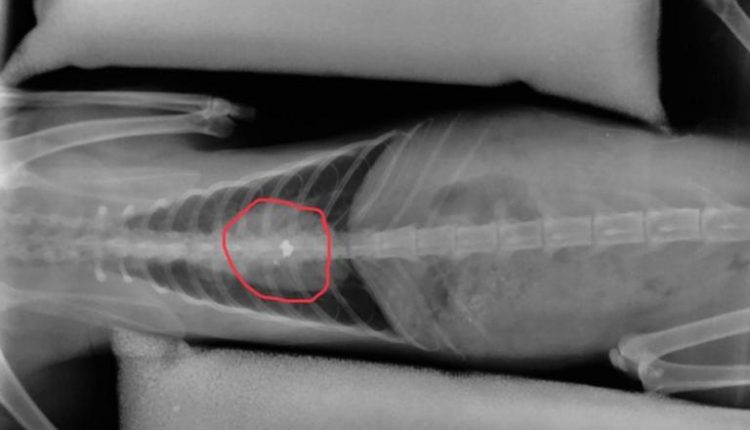

Το άτυχο ζώο δέχθηκε τη σφαίρα στην σπονδυλική στήλη, όπως δείχνουν και οι ακτινογραφίες που κατατέθηκαν στο Δικαστήριο. Ο παράλυτος γάτος, φιλοξενήθηκε προσωρινά, στο σπίτι του ανθρώπου που βρέθηκε μπροστά στο συμβάν.

Ο φιλοζωικός σύλλογος απευθύνθηκε σε ιατρείο στη Λάρισα προκειμένου οι κτηνίατροι να αποφανθούν για την κατάσταση του γατούλη αλλά και το πως θα μπορούσε να αφαιρεθεί η σφαίρα που έχει σφηνωθεί στην ραχοκοκαλιά του.